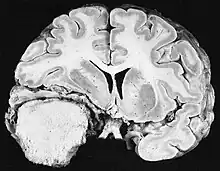

Ionizing radiation

Sources of ionizing radiation include medical imaging, and radon gas. Ionizing radiation is not a particularly strong mutagen.[73] Medical use of ionizing radiation is a growing source of radiation-induced cancers. Ionizing radiation may be used to treat other cancers, but this may, in some cases, induce a second form of cancer.[73] Radiation can cause cancer in most parts of the body, in all animals, and at any age, although radiation-induced solid tumors usually take 10–15 years, and can take up to 40 years, to become clinically manifest, and radiation-induced leukemias typically require 2–10 years to appear.[73] Radiation-induced meningiomas are an uncommon complication of cranial irradiation.[78] Some people, such as those with nevoid basal cell carcinoma syndrome or retinoblastoma, are more susceptible than average to developing cancer from radiation exposure.[73] Children and adolescents are twice as likely to develop radiation-induced leukemia as adults; radiation exposure before birth has ten times the effect.[73]

Ionizing radiation is also used in some kinds of medical imaging. In industrialized countries, medical imaging contributes almost as much radiation dose to the public as natural background radiation. Nuclear medicine techniques involve the injection of radioactive pharmaceuticals directly into the bloodstream. Radiotherapy deliberately deliver high doses of radiation to tumors and surrounding tissues as a form of disease treatment. It is estimated that 0.4% of cancers in 2007 in the United States are due to CTs performed in the past and that this may increase to as high as 1.5–2% with rates of CT usage during this same time period.[79]

Residential exposure to radon gas has similar cancer risks as passive smoking.[73] Low-dose exposures, such as living near a nuclear power plant, are generally believed to have no or very little effect on cancer development.[73] Radiation is a more potent source of cancer when it is combined with other cancer-causing agents, such as radon gas exposure plus smoking tobacco.[73]